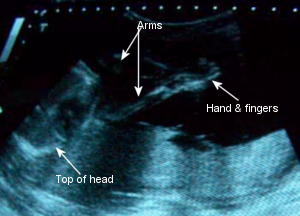

Sono Pic:

24 weeks

November 12th: I only gained a few ounces this time, so that was awesome! I had my glucose screening done on this day and flunked it by 9 points! It was supposed to be at 140 and mine was 149. Grr. I didn’t have to do the 3-hr. test because Dr. C. knows how weird my glucose is and he said, “You’re no diabetic, but I want to make a deal: keep monitoring yourself and we’ll be good.” So that’s what I have to do. Dr. C. did his measurements and she’s measuring 2 weeks less than my EDD, which is fine and she’s doing great. She’s still a girl!